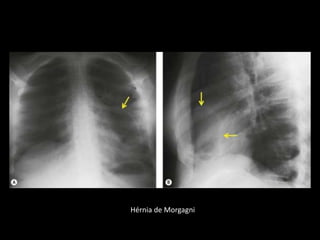

Hérnia de Morgagni